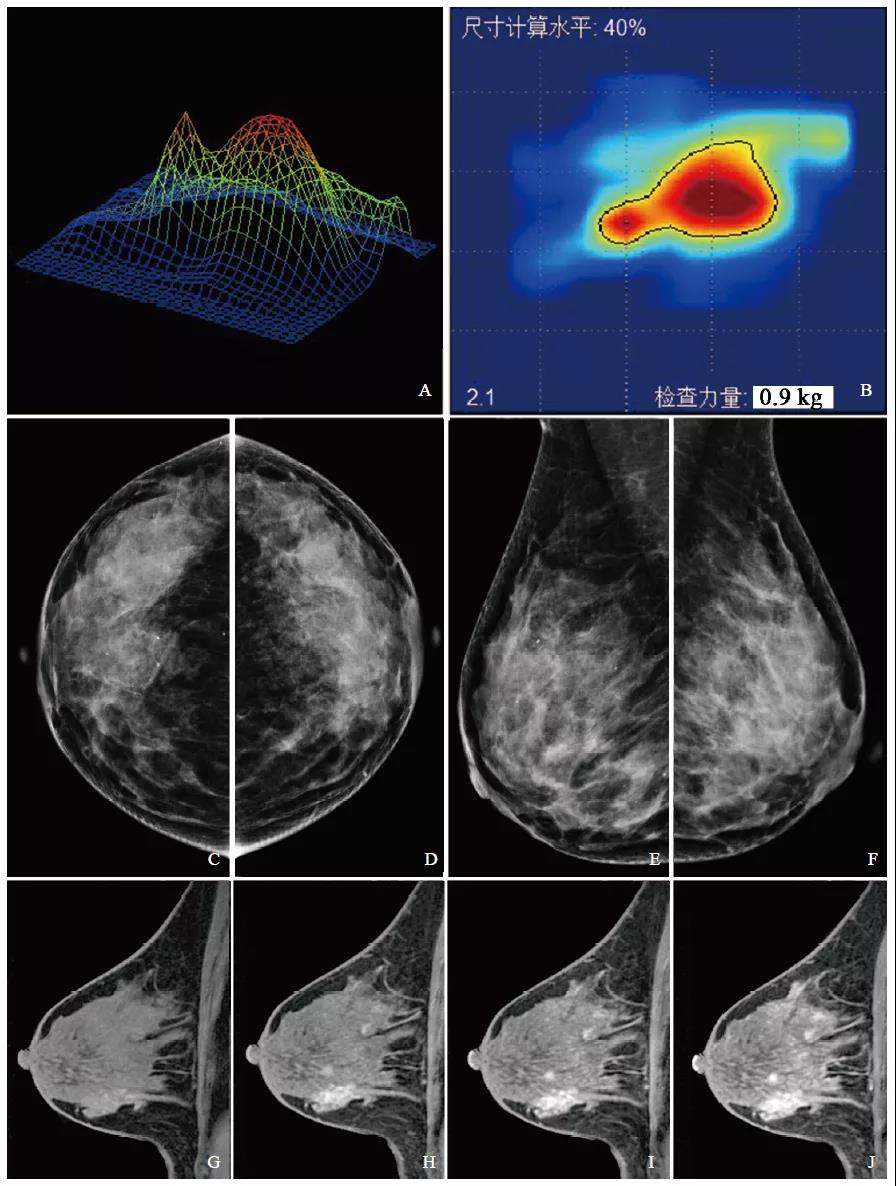

图2 右乳纤维腺瘤影像学表现

注:A、B为触诊成像检查3D及2D影像,3D图像呈单峰、峰值低、基底窄、峰顶尖,动态回放肿块活动度好;2D图像中心呈浅色、边界规则,动态回放内部结构分布均匀。C~F为乳腺X线摄影图像,乳腺X线纤维腺体类型为致密型。G~J为乳腺MRI动态增强矢状位检查图像,乳腺病变类型为肿块型。